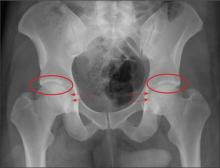

A 30-year-old man is transferred to your facility for evaluation of reported paraplegia after a fall. The patient is an inmate at a local prison. He states he was sleeping on the top bunk when he rolled over and fell off the bed, landing flat on his back on the concrete floor. He immediately started having severe back and hip pain and noticed that he could not move his legs. His primary complaint is severe bilateral hip pain. He was initially evaluated at an outside hospital, where CT of his head, cervical spine, and lumbar spine was negative for any acute pathology. He was sent to your facility for an MRI to rule out contusion or acute herniated disc. The patient denies any significant medical history, including back trauma. Currently, he reports no bowel/bladder issues or saddle anesthesia. On initial exam, he is awake, alert, and oriented, with normal vital signs. Musculoskeletal exam demonstrates a moderate amount of paraspinous tenderness and bilateral hip/pelvis tenderness. There is no instability detected, nor any leg shortening or rotation. He does have bilateral weakness in both lower extremities on the magnitude of 3-/5, although his exam seems limited due to the severity of his hip pain. Sensation is completely intact in both lower extremities. While the patient is awaiting his MRI, you order a portable pelvis radiograph, since none was performed at the outside facility. What is your impression?

The radiograph demonstrates no acute osseous injury, such as fracture or dislocation. Of interest and note is increased sclerosis within both femoral heads, more so on the left versus the right side. Given the patient’s young age, such findings could be related to early avascular necrosis. His clinical symptoms certainly correlate. MRI or bone scan, as well as orthopedic evaluation, is warranted in such a case.

Fortunately, subsequent MRI of both hips did not show any avascular necrosis but rather osteoarthritic changes. The MRI of his spinal column was negative as well.